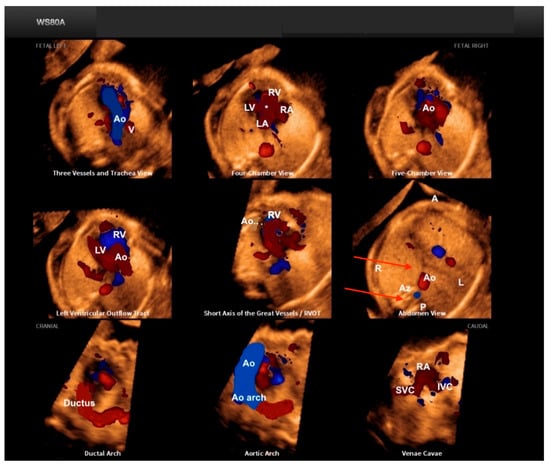

Fetal Intelligent Navigation Echocardiography (FINE), also known as “5D Heart” or “5D”, presents nine standard fetal echocardiographic views by performing cardiac volume acquisition from a 4C chamber view of the fetal heart (Figure 3) [11]. Currently, with the advent of “artificial intelligence”, the addition of this technology to 5D Heart can provide alerts for possible CHD in the images obtained via automatic reconstructions of the cardiac ultrasound views. Artificial intelligence is a promising technological innovation that can alert non-specialists to the suspicion of CHD, provide automatic measurements of image acquisition, and reduce the differences between inter-observer measurements.

Figure 3.

Fetal Intelligent Navigation Echocardiography (FINE), also known as “5D Heart”, on a normal heart. Note the automatic reconstruction of the 9 standard views of fetal echocardiography from a 4-chamber view. LV: left ventricle; LA: left atrium; RA: right atrium; RV: right ventricle; Ao: aorta; PA: pulmonary artery; SVC: superior vena cava; IVC: inferior vena cava; RVOT: right ventricle outflow tract.